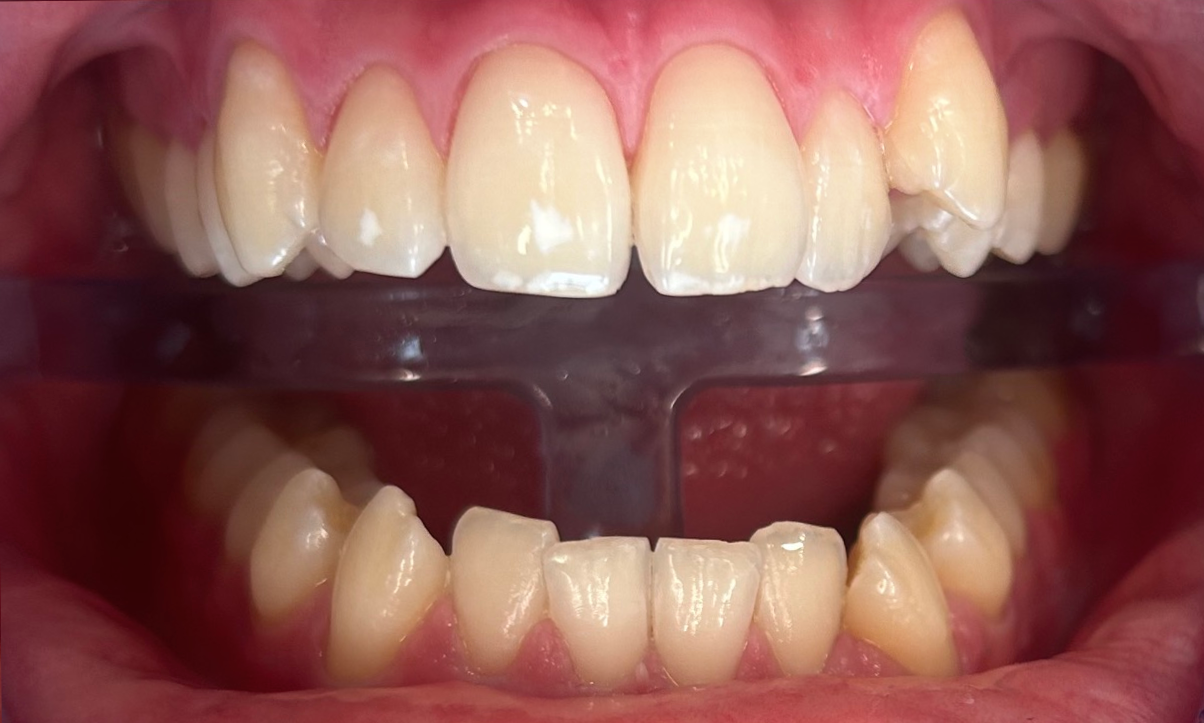

Poprawa estetyki uśmiechu: wybielanie zębów.

Profilaktyka i estetyka: usuwanie kamienia i wybielanie.